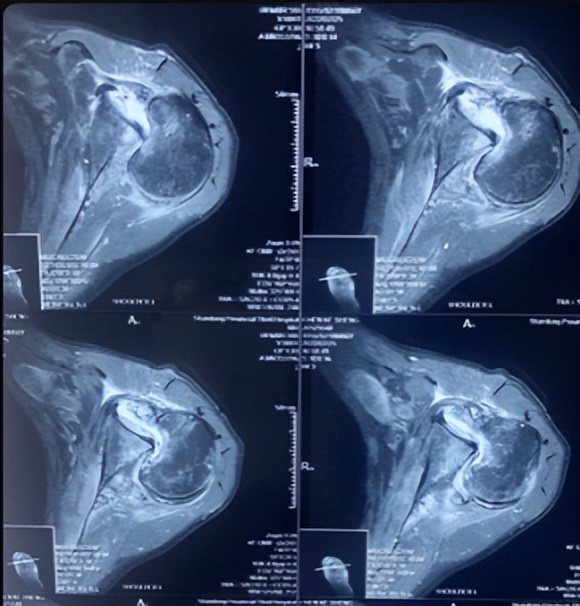

面对这例受伤时间长、脱位类型少见、骨折情况复杂的患者,创伤中心常务副主任李连欣组织全科病例讨论,通过分析认为该患者为“陈旧性绞锁性肩关节后脱位合并肱骨头骨折(反Hill-Sachs损伤)”,患者疼痛活动障碍,不能继续保守治疗,需要进行手术。患者的手术难点在于:患者为陈旧性后脱位,周围组织已经严重粘连、僵硬;脱位的肱骨头卡于关节盂造成关节面缺损,很难恢复肱骨头原本的解剖结构;合并肩袖巨大陈旧性撕裂,难以修复;患者为老年,骨质疏松明显;病程长达10年,即使手术勉强恢复其解剖关系,未来发生肱骨头缺血坏死、创伤性关节炎等并发症的几率极高。经过科室充分讨论分析,最终确定反式肩关节置换的手术方案。

肩关节脱位俗称脱臼,是临床常见损伤,后脱位少见,仅占肩关节脱位的2%, 合并肱骨近端骨折的罕见,其发病因素主要是外伤*力暴**及骨质疏松。一般临床上把骨折脱位时间在三周以上的称为陈旧性骨折或脱位。对于肩部脱位多数可以手法复位获得较好效果,新鲜骨折通过手术复位固定一般也可获得满意的效果,但对于陈旧性脱位或骨折,由于关节的挛缩、粘连等,骨折断端和周围存在大量瘢痕组织和骨痂,时间再长即导致畸形愈合,复位十分困难,也难以实施内固定。实施关节置换也存在软组织不平衡,脱位,神经损伤等风险,手术很有挑战性。